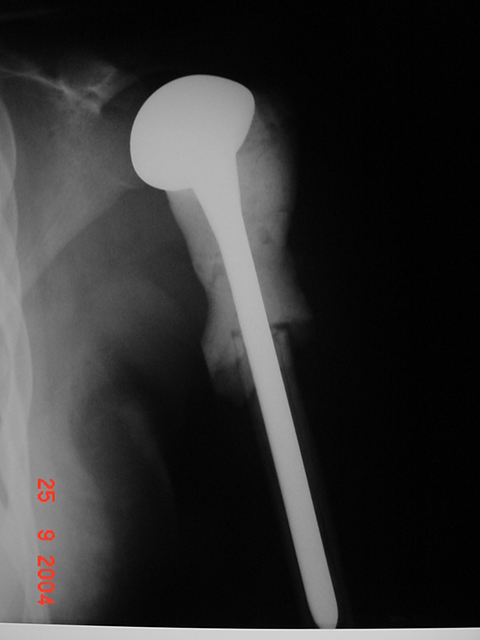

Resulta ser un tumor tipo CONDROBLASTOMA Se le opera efectuando una resección y se le

coloca una prótesis parcial. Anatomía patológica confirma un

CONDROBLASTOMA.

RADIOGRAFÍA POST OPERATORIA |